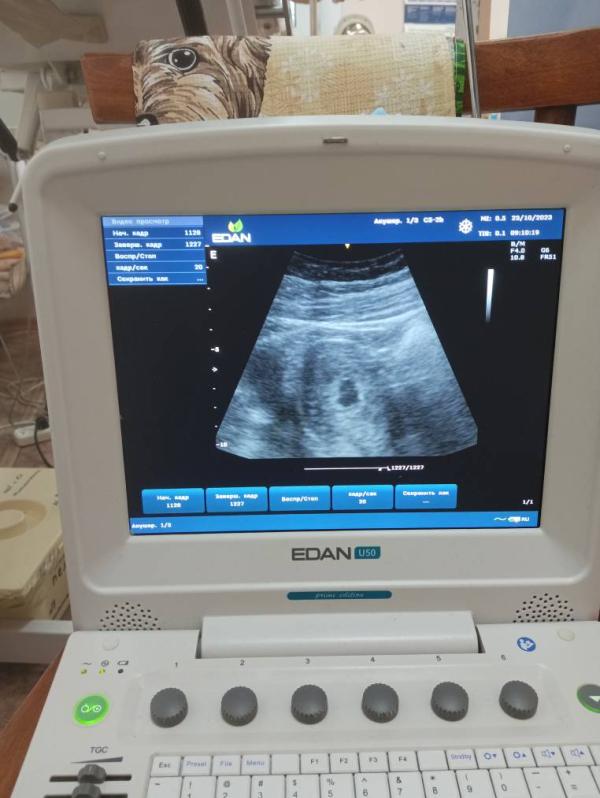

Такой интересный аппарат узи 😀

Переносной посей видимости

В кабинете у гинекологов такие бывают

Портативный, как большой толстый ноутбук)